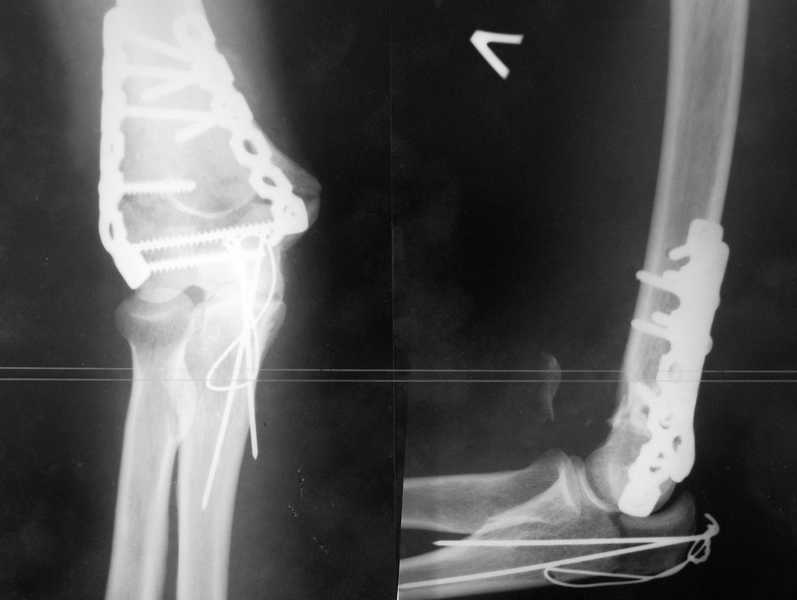

У пациентки 42 лет после операции остеосинтеза чрезмыщелкового перелома плеча, выполненной в нашей клинике 2 месяца назад, на контрольных R-граммах имеется гетеротопический оссификат по передней поверхности плеча.

Оперирована по методике АО, после операции максимально рано начала заниматся ЛФК. В настоящее время основная жалоба пациентки на ограничение сгибания в локтевом суставе. Клинически объем движений: сгибание 90 градусов, разгибание 170 градусов, ротационные движения в полном объеме. Привожу снимки сразу после операции и через 2 месяца. (На рентгенограммах после операции в мягких тканях по передней поверхности плеча имеется небольшой костный фрагмент, но его ширина во фронтальной плоскости не более 1 мм., обнаружен был по снимкам после операции. Интраоперационно основные крупные фрагменты отрепонировались хорошо, объем движений был сгибание до 75 градусов, разгибание 175 град.)